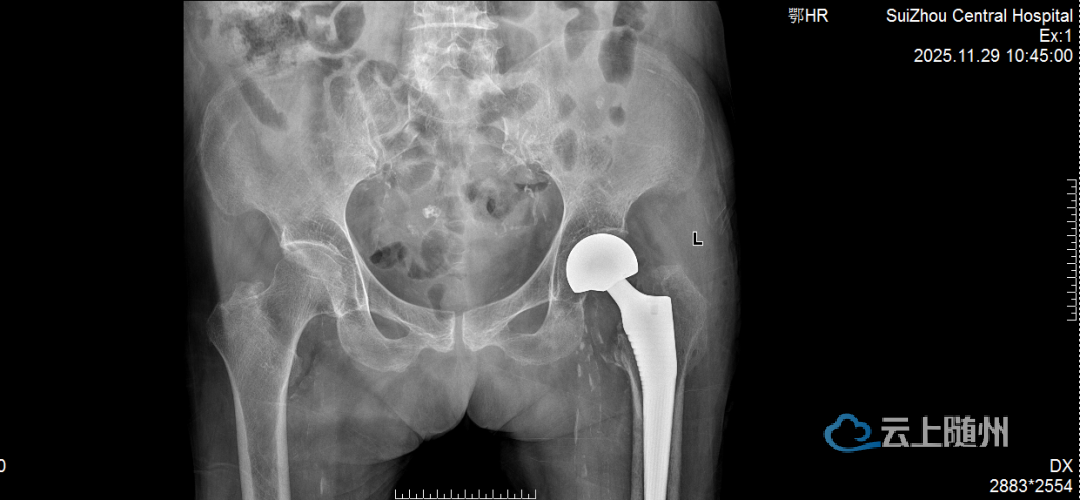

在充分的术前准备与精细的术中操作下,团队成功为患者实施人工髋关节置换术。手术时间短、出血少,极大减轻了患者身体负担。术后,在护理团队的精心照护与康复指导下,老人恢复良好,疼痛显著缓解,生活质量大幅提升。看着老伴重露笑容,老先生感激满怀。

术前术后